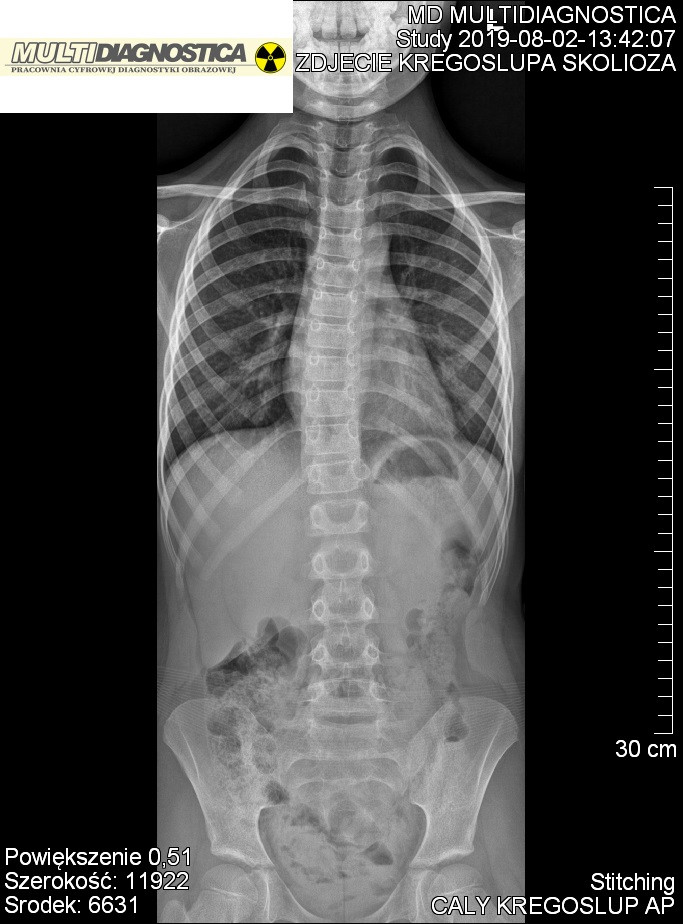

RTG Telemetryczne Kraków Prądnik, RTG Posturalne Kraków Prądnik, RTG Skalometryczne Kraków Prądnik, Stitching Kraków Prądnik

Wyposażyliśmy pracownię w cyfrowy detektor z oprogramowaniem posiadającym funkcję skalometrii (Stitching), dzieki której możliwe jest wykonanie badania telemetrycznego RTG całych kończyn długich i całego kręgosłupa a następnie uzyskanie obrazu diagnostycznego obejmującego razem kilka części anatomicznych połączonych w całość.

Pomiary długości kości kończyn, kątowe pomiary skrzywień kręgosłupa